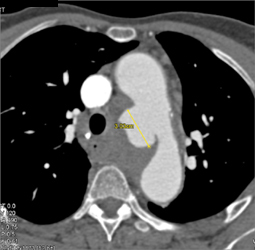

Pulmonary Atresia With A Stent in the Right Pulmonary Artery